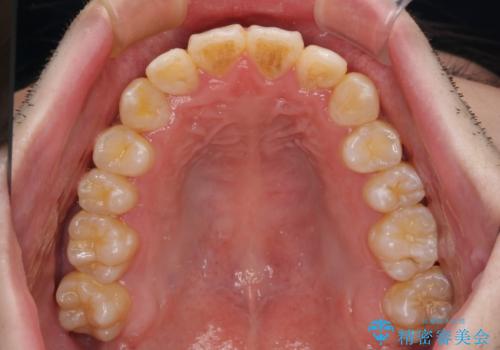

全顎的なクロスバイト 補助装置を用いてワイヤー矯正

前歯のクロスバイトや八重歯の他に、左右最後臼歯のシザーズバイト(鋏状咬合)が認められました。

シザーズバイト改善のために補助装置を使用しながら、ワイヤー装置にて全体の歯列を整えることとしました。